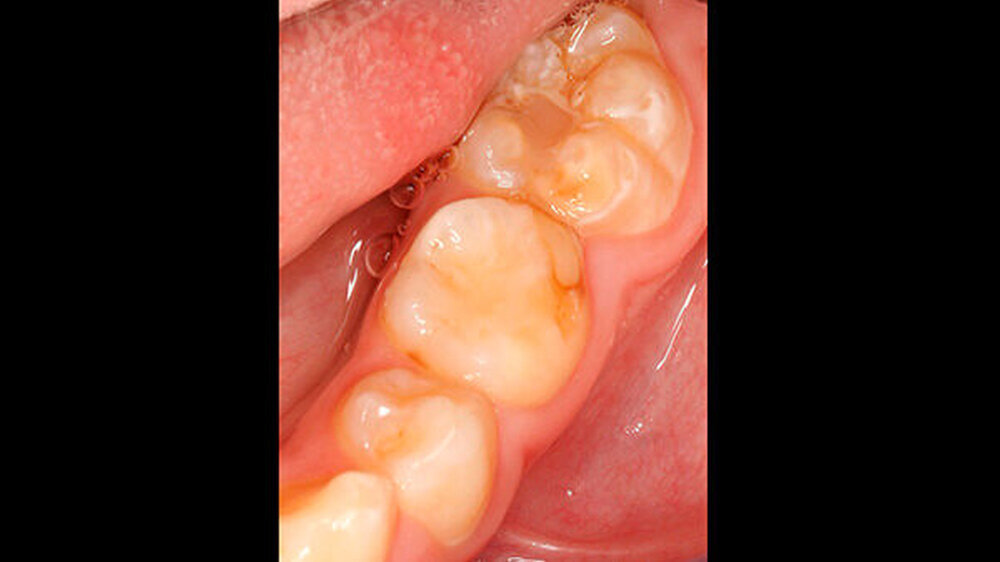

Der Zahnwechsel im 2. Quadranten war noch nicht vollständig, dasselbe galt für den Unterkiefer (Abbildungen 4 und 5). Im Unterkiefer war insbesondere die Opazität und der bukkale Schmelzeinbruch (inklusive der Reste einer adhäsiven Füllung) an Zahn 85 deutlich sichtbar.

Zusätzlich wiesen beide Sechsjahrmolaren im Unterkiefer insbesondere im Bereich der Höcker (46) sowie der Höckerspitzen (36) ebenfalls Opazitäten auf, deren farbliche Veränderung von milchig-weiß bis hellbraun reichte. Zahn 46 war darüber hinaus mit einer erweiterten Fissuren-Versiegelung oder einer kleinen okklusalen Füllung versorgt. Das Trocknen der Seitenzähne mittels Luft rief ein geringfügiges Schmerzgefühl bei dem Patienten hervor, an Zahn 26 allerdings eine starke Sensibilität.